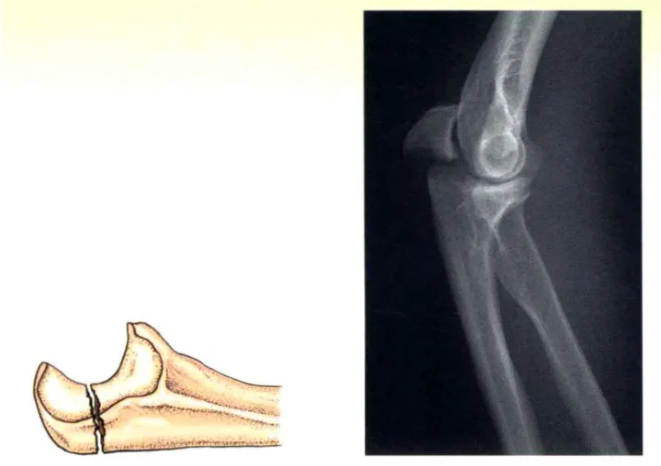

A型(xing):簡單(dan)橫形骨折(zhe)

A型(xing):張力帶固定的經典類(lei)型(xing),接(jie)骨板和螺釘固定也顯(xian)示有(you)效。